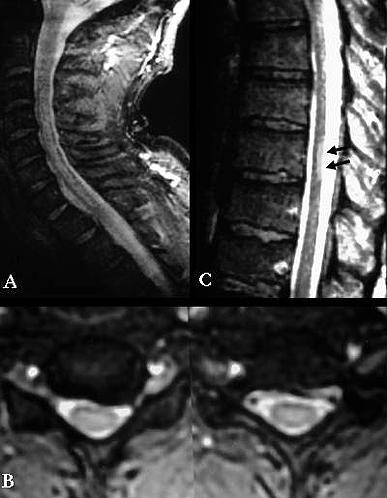

Estes dados implicam que o mergulho pode produzir danos subclínicos ao cérebro, medula espinhal (Fig. 2, 3), ouvido interno, retina e pequenas vias aéreas do pulmão. Outros estudos sugerem diminuição significativa das funções pulmonares e cognitivas.

A ressonância magnética (MRI) deu aos investigadores uma ferramenta adicional para estudar o sistema nervoso central em mergulhadores. Com a ressonância magnética, foi relatada alta intensidade de sinal (pontos brilhantes), indicando danos nos tecidos, em mergulhadores e acredita-se que tenha grande potencial para identificar danos causados ao SNC.

Foi usado pela primeira vez pelos noruegueses (Todnem e associados) para estudar doenças descompressivas, e eles descobriram que até 33% de todos os mergulhadores apresentavam alterações de alta intensidade de sinal. Estudos semelhantes realizados por Brubakk e Rinck e colaboradores confirmaram essas descobertas.